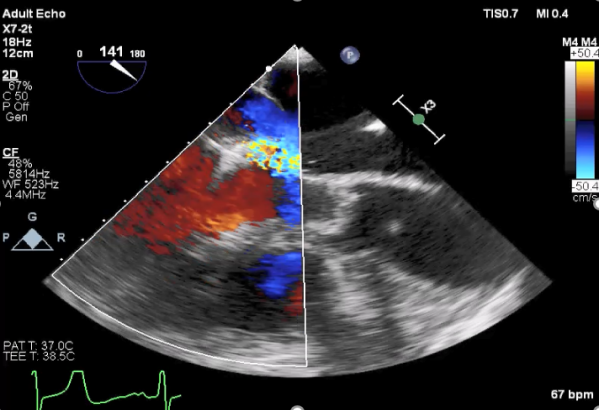

麻醉状态下TEE显示中大量返流MR:

患者麻醉方式采取全麻,建立静脉通路后,穿刺右侧股动脉以及股静脉,预埋ProGlide缝合器,冠脉造影复查提示支架通常。TEE超声指导下经房间隔穿刺后进入左房,送入鞘管,MitraClip调整后顺利到达二尖瓣目标位置,后在X线及食道超声辅助下,使用1枚XTR二尖瓣夹准确夹合二尖瓣A2-P2区,超声即刻测反流面积明显减少,LVOT切面,四腔心切面以及3D下证实夹合组织充分,患者收缩压由术前的108/62mmHg上升至130/72mmHg,左心房压力显著减低,肺静脉多普勒波形由反向恢复正常。手术顺利结束,安返普通病房。

XTR夹子释放,返流明显减少

术后肺静脉频谱

二尖瓣瓣口面积及平均跨瓣压差评估(4mmHg)